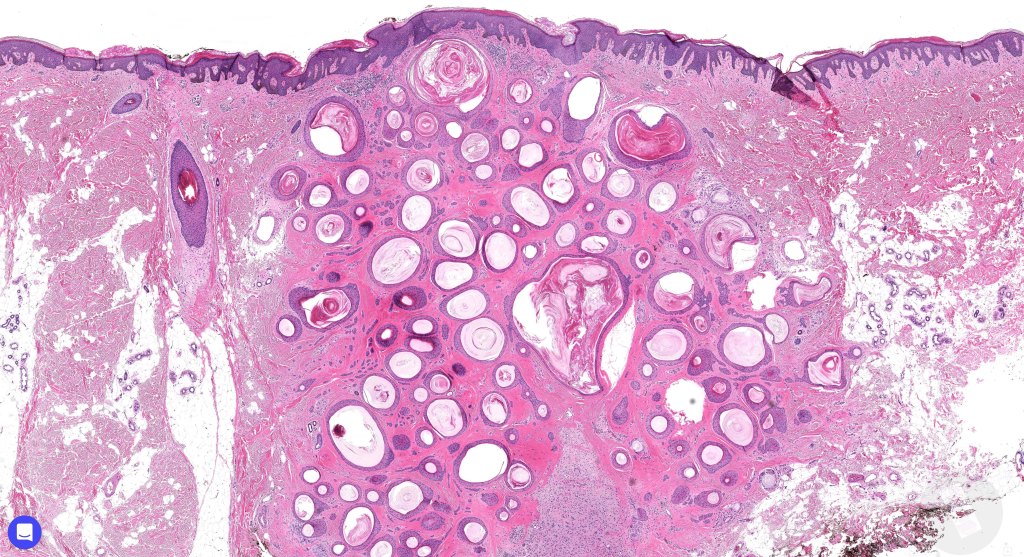

A rare benign tumor showing differentiation towards the infundibular portion of the pilosebaceous canal. Some authors postulate that it occupies a place miday between trichoepithelioma & trichofolliculoma.

•Keratocysts showing infundibular keratinization i.e.with a granular cell layer

•Solid epithelial islands

•Fibrovascular stroma